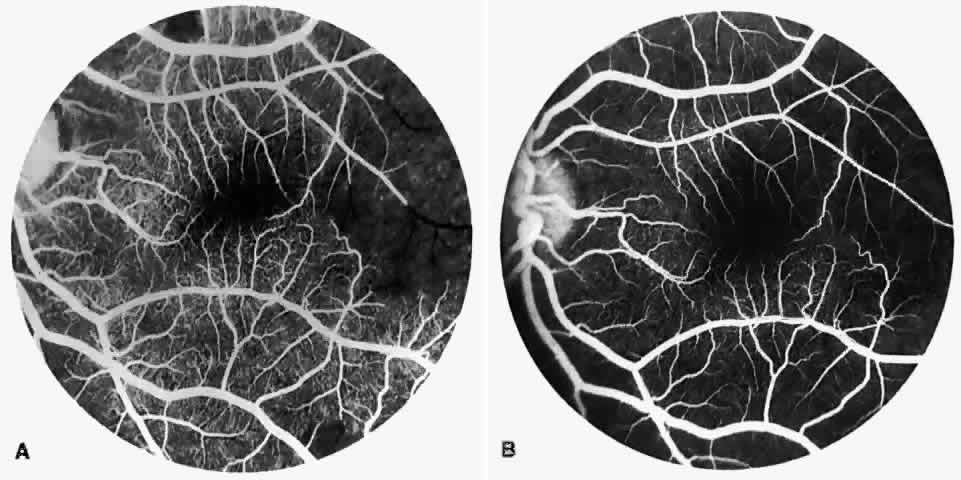

Vascular Tortuosity

Dilation and tortuosity of the retinal veins was one of the first recognized abnormalities of sickle cell eye disease. Although it is not pathognomonic of sickle cell disease, it reportedly occurs in up to 47% of patients with homozygous sickle cell anemia and 32% of patients with SC disease (Fig. 4).70 The significance of this venous tortuosity is unknown, and the incidence does not appear to be related to age.71

Fig. 4. A. Generalized vascular tortuosity, predominantly venous, in a patient with homozygous sickle cell anemia. B. Localized macular venous tortuosity in a patient with SC disease.